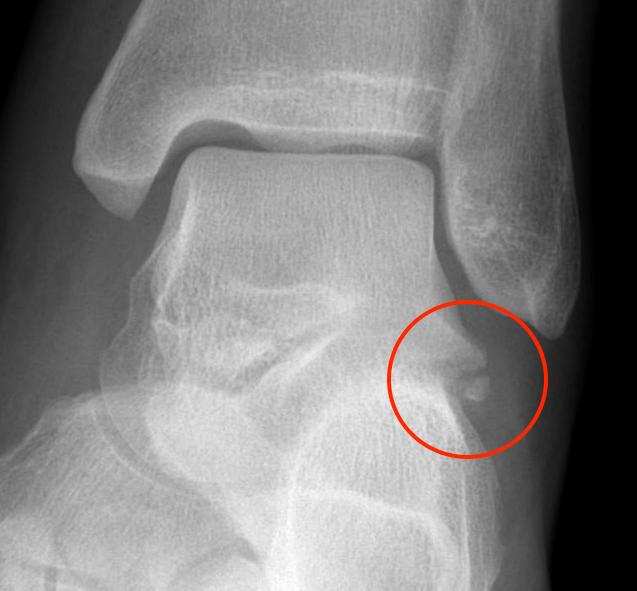

X-ray

Best seen on mortise view